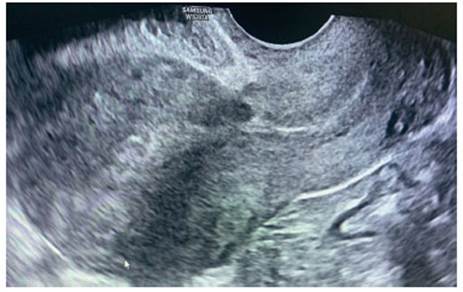

Al 6to día, la βhCG estaba en 2,097 UI/L. Se realizó nuevo estudio ecográfico, con visualización de canal cervical y cavidad uterina sin contenido y a nivel de la cicatriz de la cesárea previa se apreció una imagen compatible con saco gestacional de 24 x 18 mm, sin presencia de vesícula vitelina ni polo embrionario en su interior (figura 1). El modo Doppler presentó mapa color positivo (figura 2). Los anexos fueron normales y no se vio líquido libre. Ante la alta sospecha de gestación ectópica sobre cicatriz de cesárea previa, se indicó tratamiento con manejo médico. Se administró una dosis única de metotrexato intramuscular a dosis de 50 mg/m2 de superficie corporal, correspondiéndole 95 mg, con correcta tolerancia. Entre el cuarto y séptimo día postratamiento, la paciente mostró descenso de la βhCG superior al 15% (17,7%). Pero, ante la persistencia de la imagen ecográfica, se decidió administrar una segunda dosis de MTX intramuscular 95 mg. En los controles posteriores, la paciente se encontraba asintomática y los valores de βhCG presentaron descenso progresivo, llegando a negativizarse a las diez semanas de la administración de la segunda dosis de MTX. Además, en la ecografía de control se apreció la involución del saco gestacional sobre la cicatriz de la cesárea (Figura 3).

Figura 1 Ecografía transvaginal. A) Corte sagital con hallazgo de gestación ectópica tipo 1 sobre cicatriz de cesárea. B) Ampliación de la imagen anterior para medición del saco gestacional (24 x 18 mm).

Figura 2 Ecografía transvaginal con modo Doppler. Se aprecia mapa color positivo alrededor del saco gestacional.